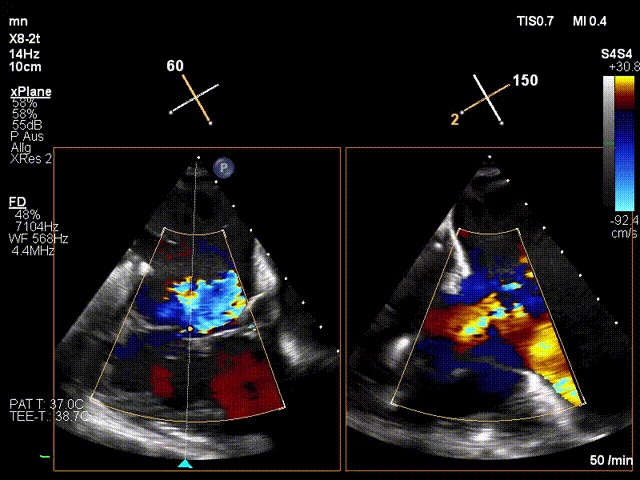

手術(shù)在全麻狀態(tài)下進(jìn)行。在加拿大圣保羅醫(yī)院的Anson Cheung教授的指導(dǎo)參與下,術(shù)者采用經(jīng)右側(cè)頸靜脈入路的方式將輸送器送入患者心臟內(nèi),在TEE及DSA引導(dǎo)下調(diào)整輸送器頭端角度,使得輸送器與三尖瓣瓣環(huán)平面垂直。在輸送器進(jìn)入右心室后釋放室間隔錨定裝置,而后釋放瓣葉夾持件(2個(gè)耳片結(jié)構(gòu))成垂直狀態(tài)。在TEE及DSA確定夾持件固定至三尖瓣葉根部且位于右室側(cè)后釋放人工瓣心房側(cè)盤片。隨后調(diào)整瓣膜同軸性以及室間隔錨定件位置(貼合室間隔),前推藏針管并固定,進(jìn)而釋放室間隔錨定裝置,并再次確認(rèn)瓣膜位置、穩(wěn)定性及同軸性,合攏輸送鞘后撤出輸送器,完成LuX-Valve Plus人工三尖瓣瓣膜的植入。

LuX-Valve Plus經(jīng)血管三尖瓣置換系統(tǒng)本次“出海”圓滿完成,術(shù)后Jörg Hausleiter教授對(duì)LuX-Valve Plus經(jīng)血管三尖瓣置換系統(tǒng)的器械性能和治療效果大為稱贊,認(rèn)為L(zhǎng)uX-Valve Plus的手術(shù)體驗(yàn)非常好。術(shù)后即刻超聲顯示三尖瓣反流消失,血流動(dòng)力學(xué)改善顯著,患者恢復(fù)快。Anson Cheung教授也肯定了LuX-Valve Plus術(shù)中操作的便捷性,認(rèn)為L(zhǎng)uX-Valve Plus容錯(cuò)率高,對(duì)術(shù)中影像的依賴較小,后期希望可以更多的應(yīng)用LuX-Valve Plus三尖瓣置換系統(tǒng)于臨床實(shí)踐,讓更多的三尖瓣重度反流患者盡早獲益,改善預(yù)后。